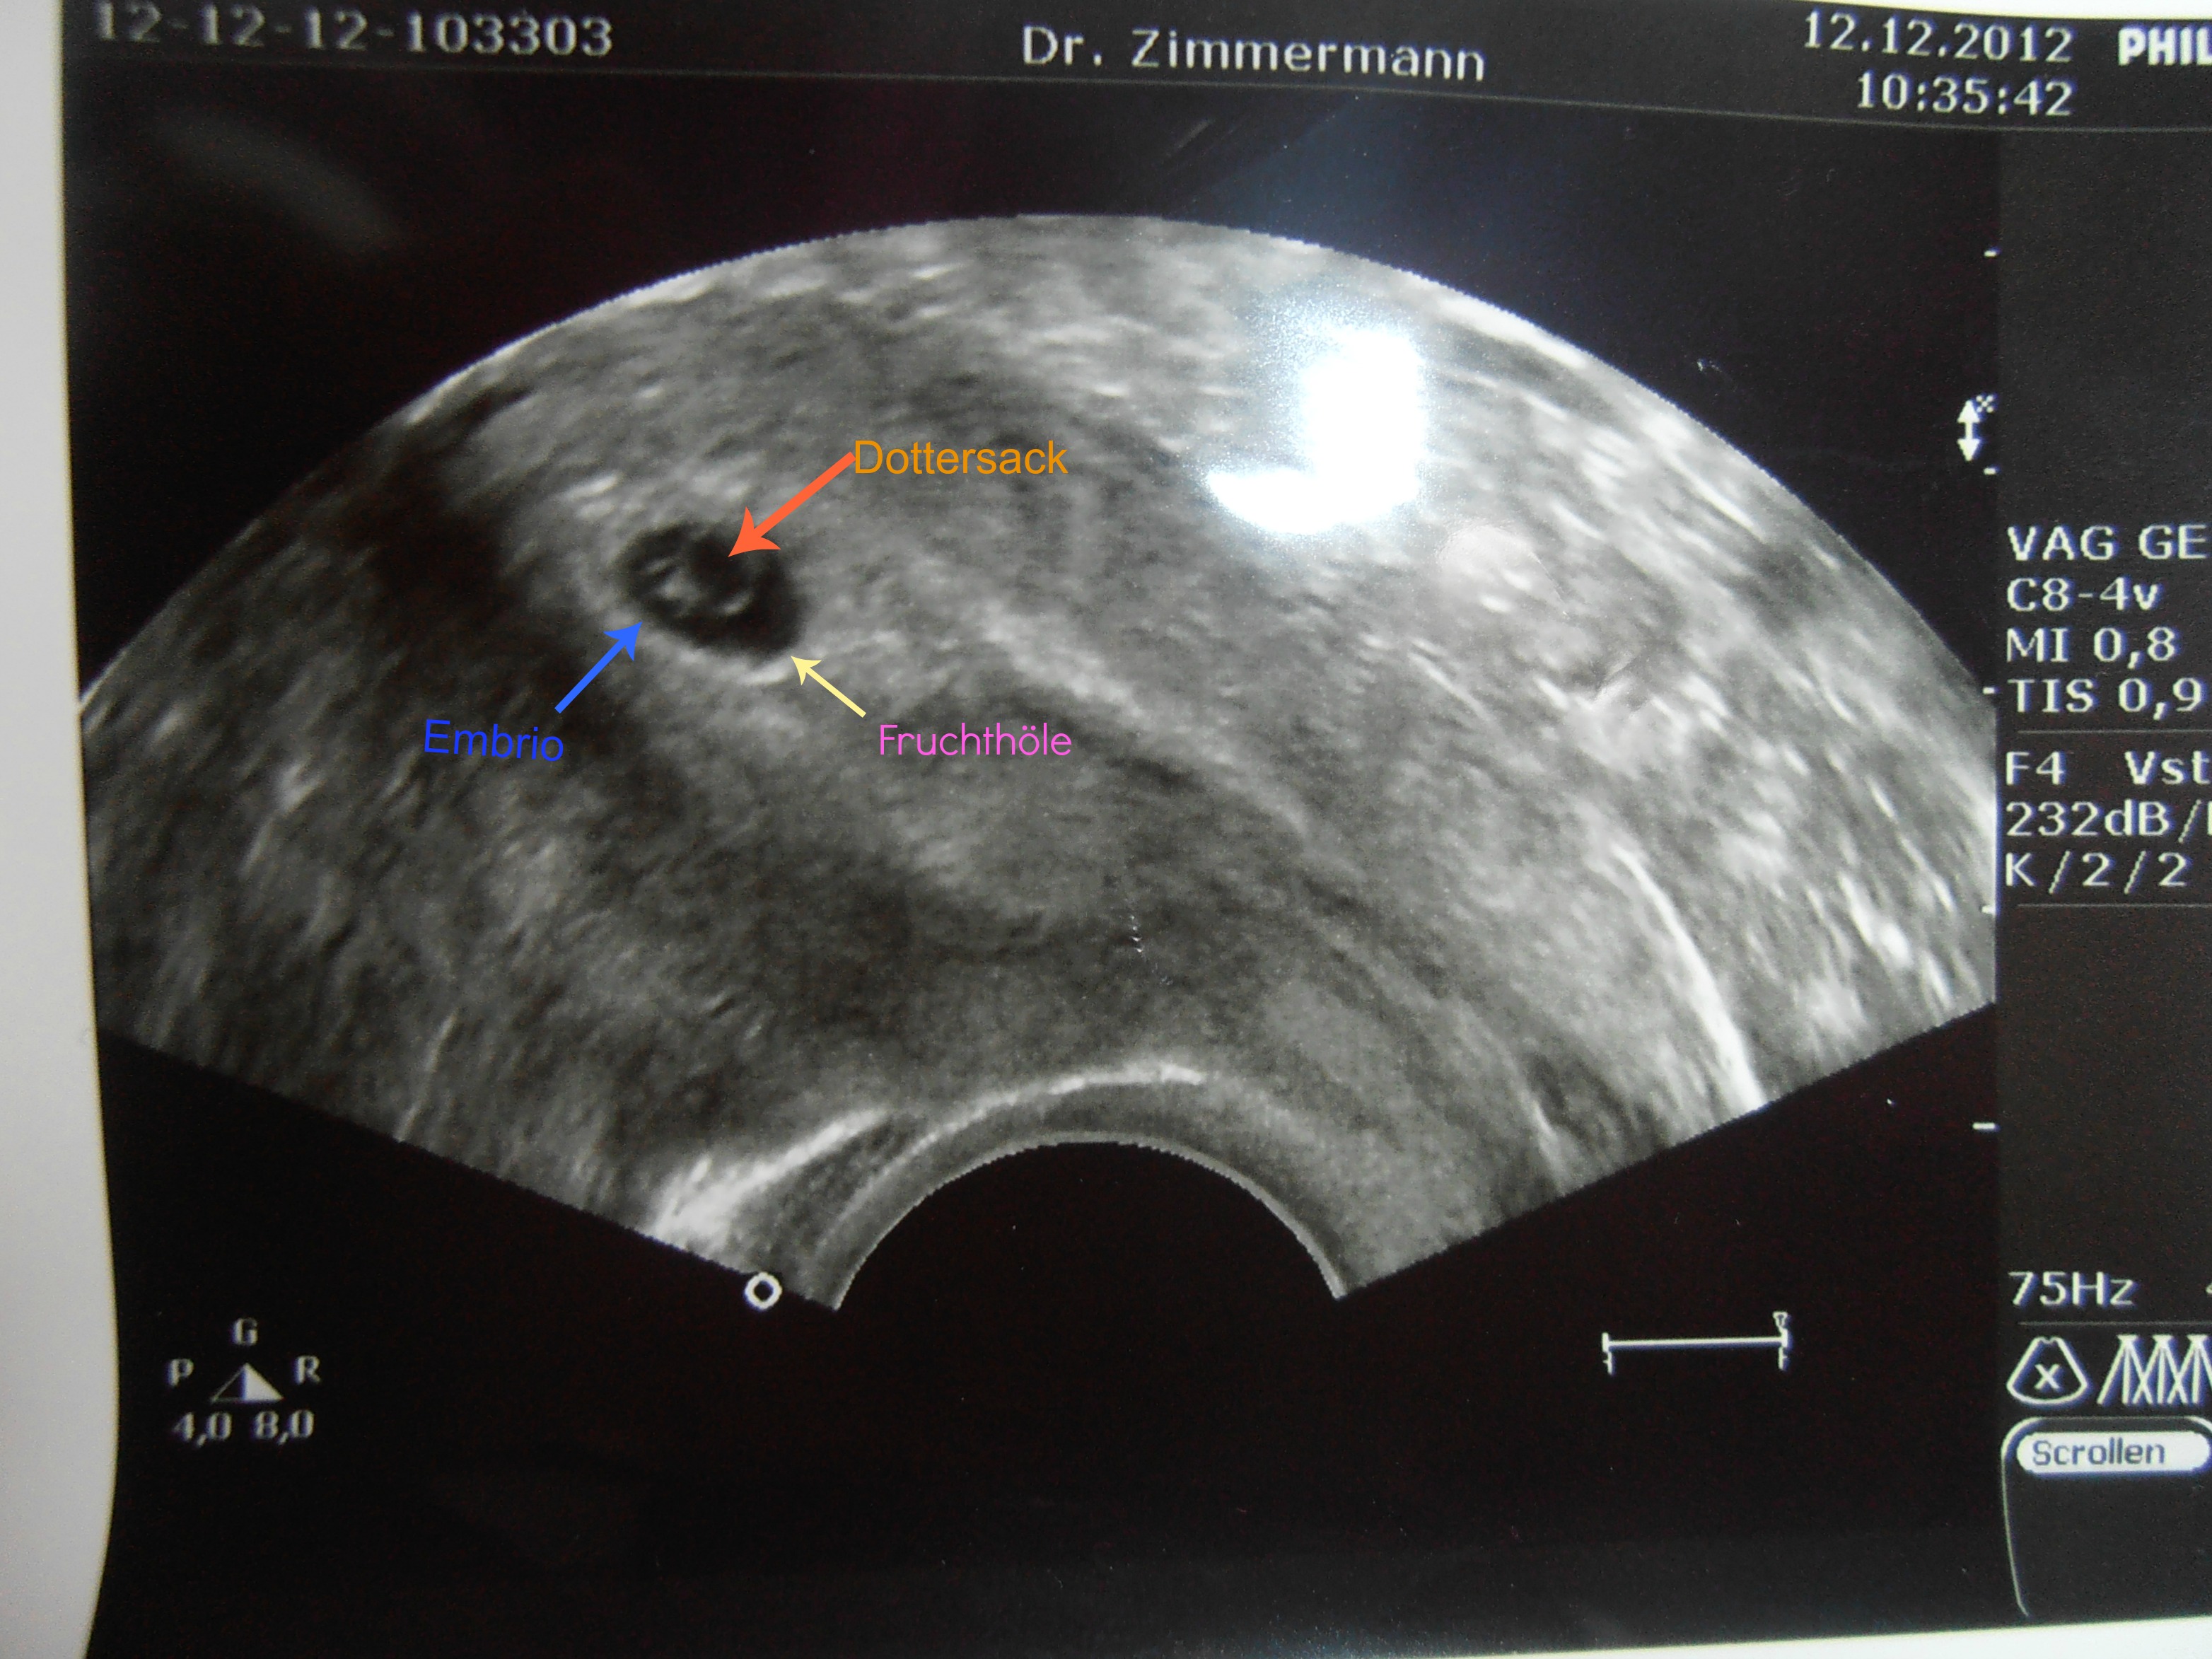

Auf jedenfall sieht man jetzt schon mehr auf dem Ultraschallbild :)

Was doch zwei tage ausmachen....